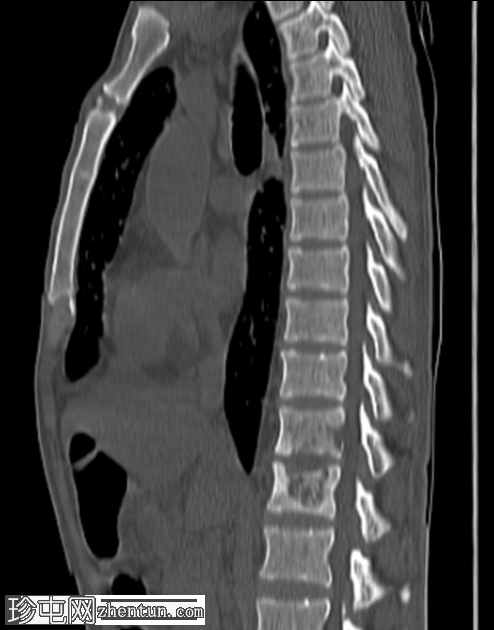

矢状骨窗

T11和T12对侧椎体终板糜烂性改变及皮质下溶骨性病变,伴右侧椎前小软组织病变。